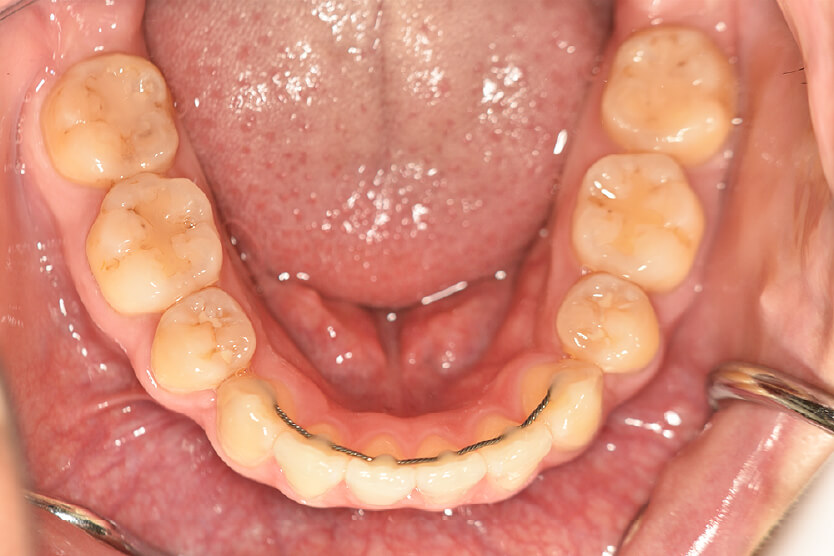

初診時

症例 症例 症例 症例

年齢

21歳 性 別 女性

治療内容の詳細 初診時21歳の女性で、出っ歯、下顎前歯部のがたつきを気にされ来院されました。

検査の結果、上顎前突、上下顎前歯部叢生および開咬を伴うアングルⅡ級1類不正咬合と診断しました。

治療としては、上下左右第一小臼歯を抜歯して、セルフライゲーションブラケット装置(デーモンシステム)とマウスピース型矯正装置(インビザライン)で配列を行いました。

この際、上顎に歯科矯正用アンカースクリューを設置し上顎前歯部後退時の土台としました。

開咬については、顎間ゴムの協力もあり改善されました。